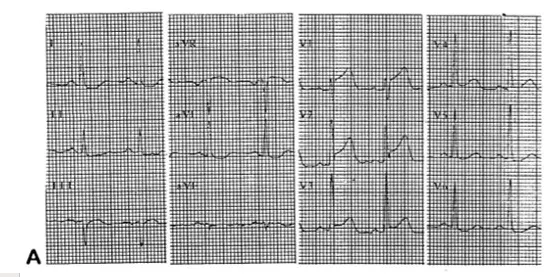

A. A. flutter ->atrial infarction 동반된 inferior infarction

B. PR segment displacement -> atrial infarction

V1 STE, V2 STD -> right sided series 꼭 찍어봐야한다 (RV infarction)